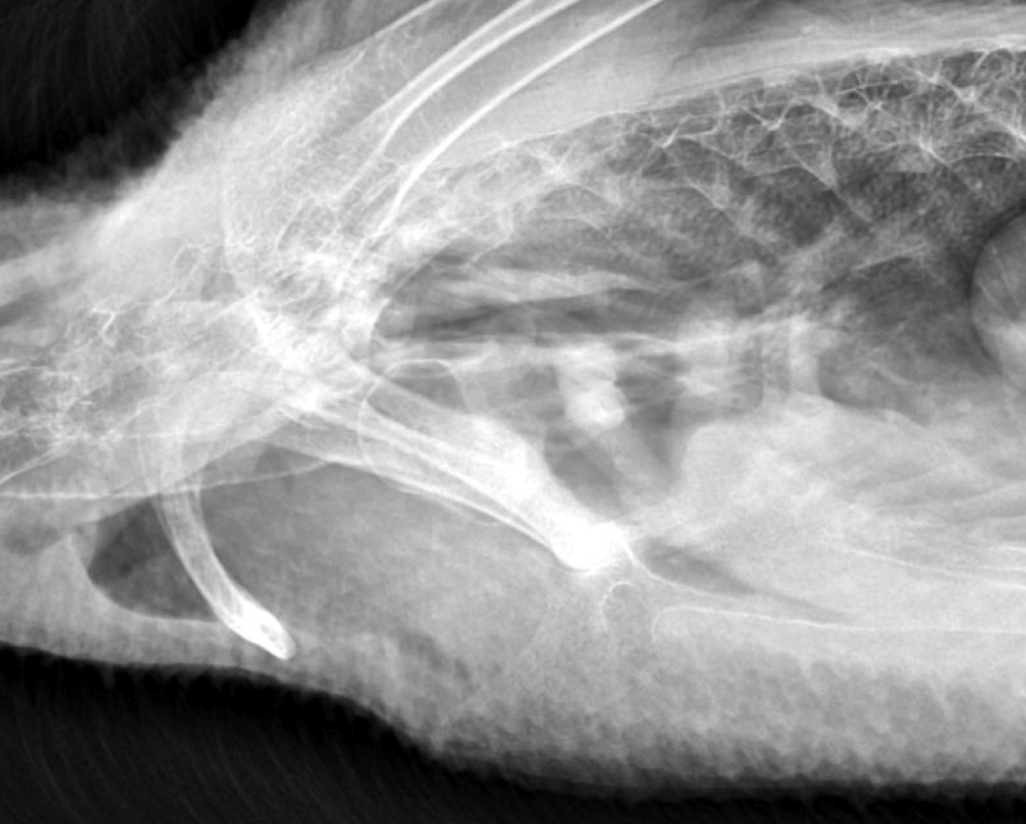

Whats wrong?

pneumonia